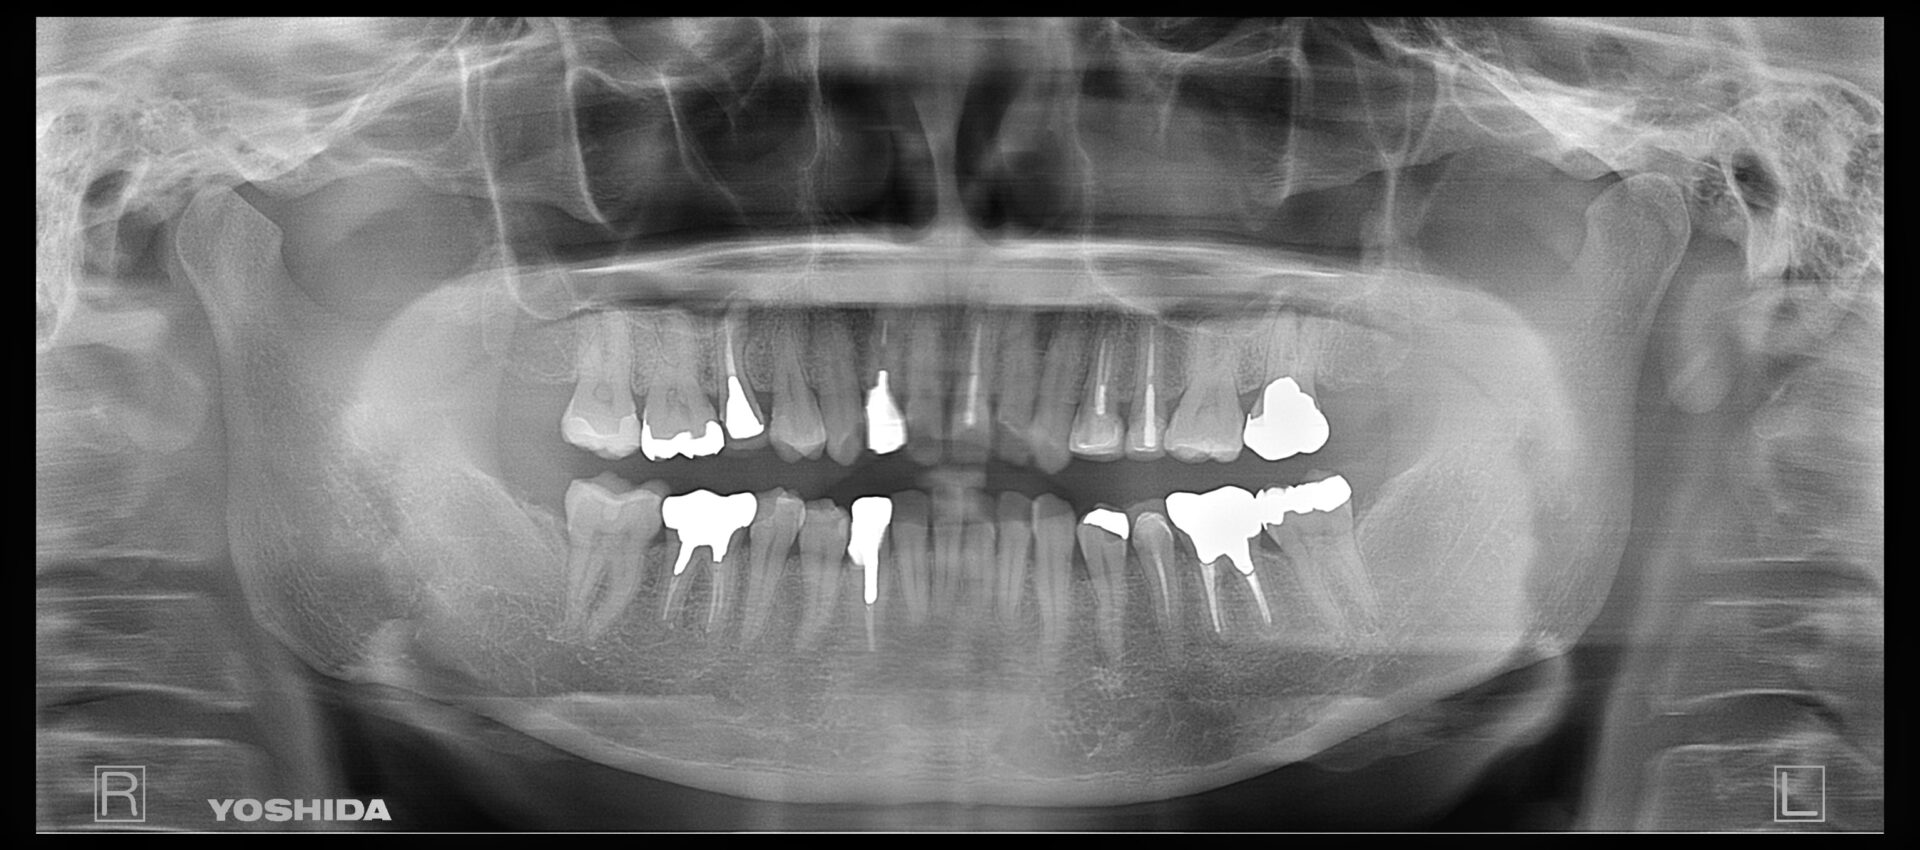

Case

40代 女性

当院にて他院で根管治療中ですがお痛みがとれないとのことを主訴にお見えになりました。レントゲン画像にて右下に膿の袋の黒い部分を認めます。歯の破折などがないか調べて問題なさそうでしたので治療を開始してゆきます。

当院にて精密根管治療(保険診療)を受けていただきまして、その後レントゲンにて膿の袋の消失を認め経過良好に治癒しています。最後はジルコニアクラウンにて修復しており術後3年で経過良好です。

最終的な被せ物はジルコニアクラウンです。

費用 | 10万円 |

---|---|

治療期間 | 4か月 |

注意事項(リスク・副作用など) | 治療後数時間から数日後に、痛みや腫れが生じる場合があります。 |

カテゴリ | 歯内療法 |